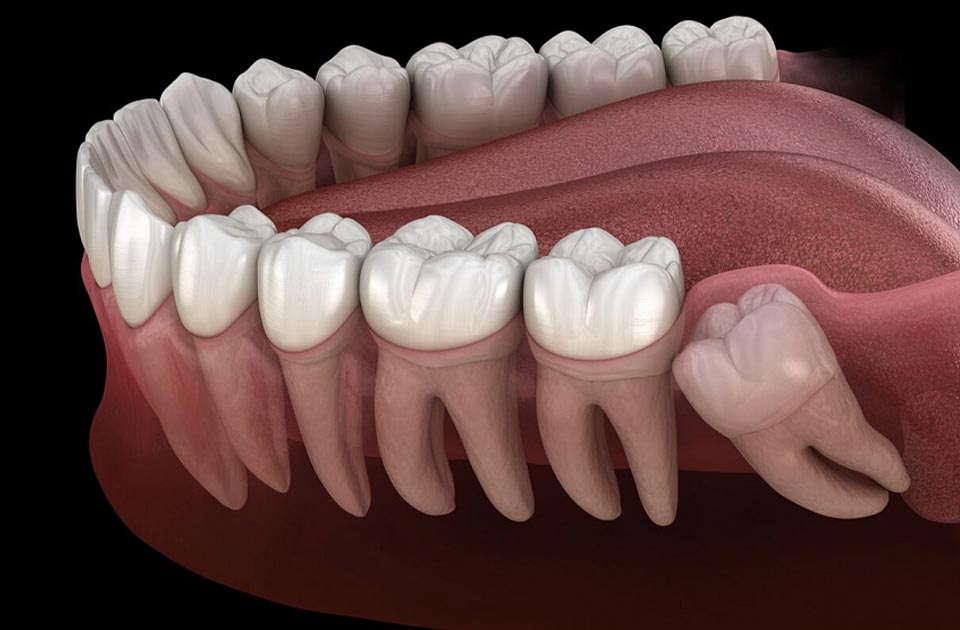

دندان های دندانی سوم دندان های دائمی هستند که در بزرگسالی از 18 تا 25 سالگی فوران می کنند. بسیاری از دندانپزشکان دندان عقل را آتاویسم می دانند و حذف دندان عقل را توصیه می کنند ، زیرا به عنوان یک واحد عملکردی ، دندانی شدید و بی فایده هستند. دندان های بزرگ و قدرتمند جویدن توسط انسان اولیه برای جویدن غذای خام قبل از آتش زدن مورد نیاز بود. مردم مدرن از چنین محصولاتی استفاده نمی کنند ، بنابراین نیاز به دندان های دندان سوم در طول 300 هزار سال گذشته ناپدید شده است.

دیستوپیا یا محل اشتباه دندان : دندان عقل با زاویه رشد می کند. چنین دندان هایی بیشتر تحت تأثیر پوسیدگی قرار می گیرند ، کج می شوند ، در برابر دندان های کناری هستند و آنها را جابجا می کنند و نیش را مختل می کنند;

احتباس: دندان عقل در لثه باقی می ماند یا تا حدی فوران می کند. که اغلب باعث التهاب و درد شدید از بالا یا پایین فک می شود ، بنابراین برداشتن دندان عقل زیر لثه تنها راه حل مشکل است;